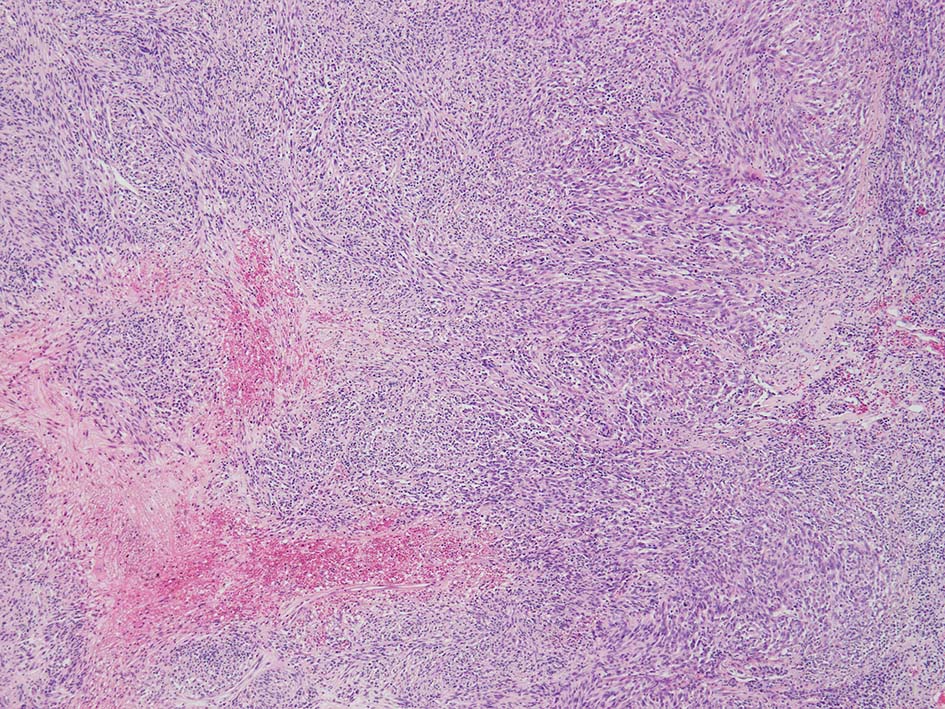

SPS244-Case01 右下眼瞼腫瘤 70歳代女性

リンパ濾胞が細血管周囲に形成され, この部分に異型といえる細胞が増加している(S100+)

再発腫瘤病変の組織像